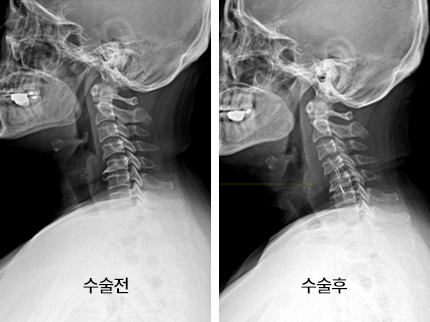

시술로써 눈에 띄게 질환을 현저히 치료하시는 것이 아니라 염증을 보완하고 통증을 낮추는 것이 포인트입니다. 이러한 방식으로 비 수술적인 치료를 3개월 이상 넘었음에도 불구하며 증상이 호전을 보이지 않으신다면 목디스크 치료방법 중 수술적 치료를 고심해야 하더라고요. 인공디스크를 투입하기 위함으로 절개를 통하기에 디스크를 제거하며 뼈를 하나로 유합 시켜서하는 것과, 내시경 수술로 빠져 나온 수핵 자체만을 제거시켜서하는 방법이 있다고하고요.

수술 방법에도 많은가 있다고 하는데 개괄적으로 설명을 하면 목을 절개해 망가진 디스크를 제거한 뒤 뼈를 하나로 유합하는 방법, 인공 디스크 투입술, 내시경을 활용해 바깥으로 빠져나온 수핵을 없애는 수술법 등이 있다고 합니다.